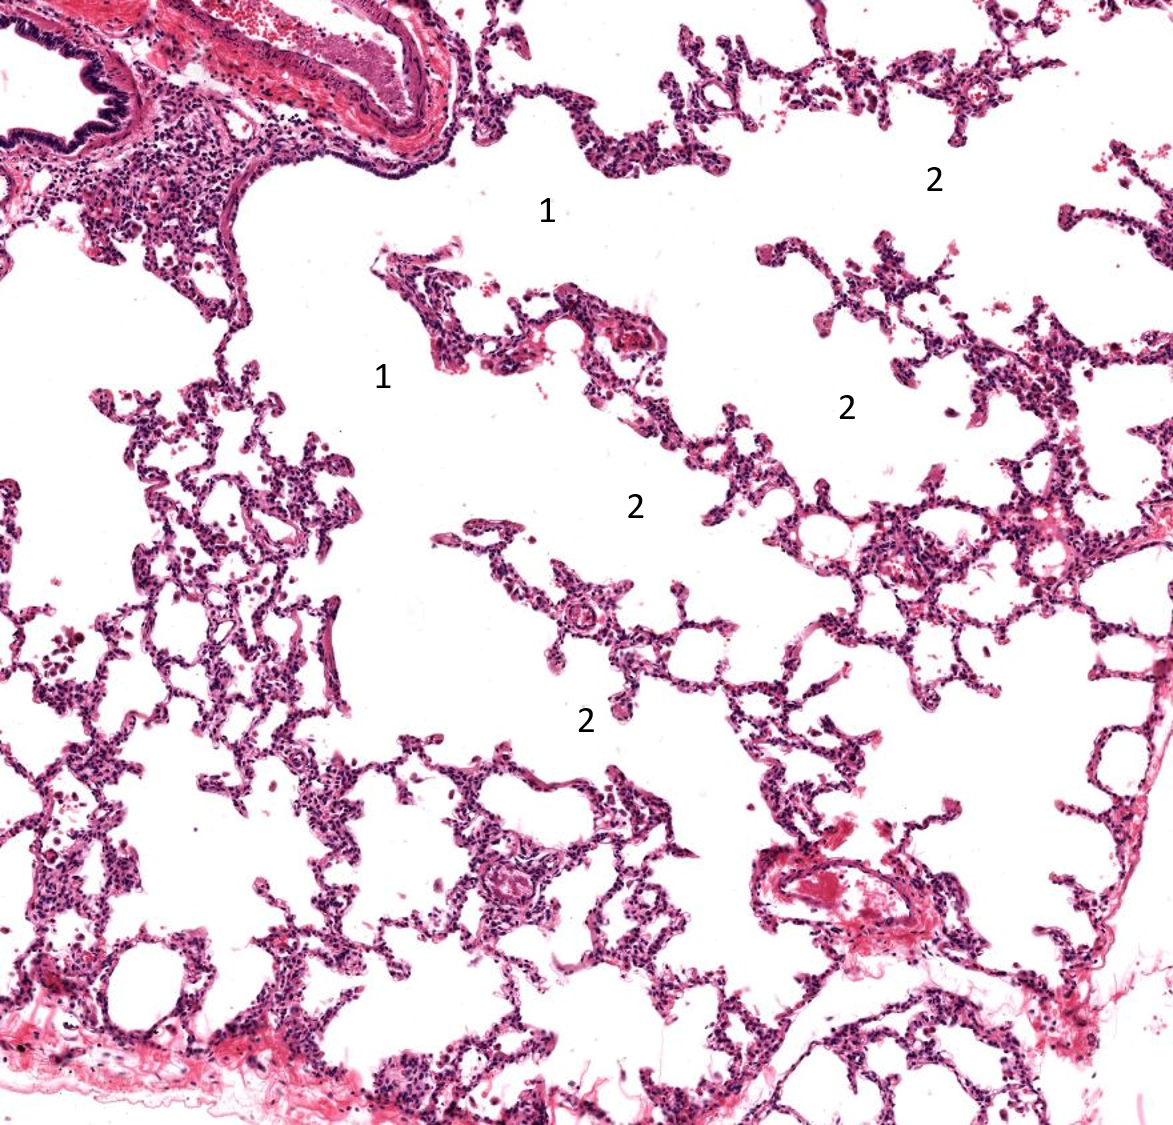

1: Bronquiolo respiratório

2: Ducto alveolar

1: Bronquiolo respiratório

2: Ducto alveolar